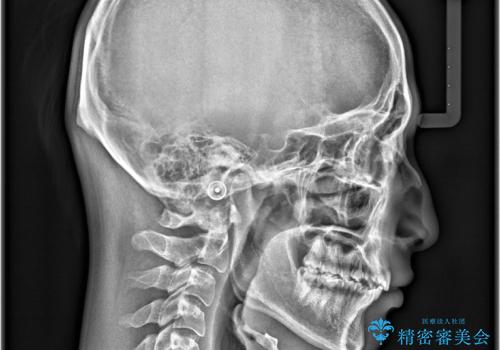

- 咬み合わせの不調和と歯並びのデコボコを主訴にご来院された患者様です。

精密矯正検査の結果、歯を抜かずに非抜歯でワイヤー矯正で治療を行う方針としました。

叢生(歯のデコボコ)の量が多く、加えてディープバイト(過蓋咬合)や重度の捻転も認められたため、リンガルアーチやマイクロインプラントなどの補助装置を併用し、治療を進めました。

治療途中では咬み合わせの改善を目的としてバイトアップを行い、歯の捻転や叢生を改善しつつ、機能的に安定した咬合を獲得しています。

治療期間は3年2ヵ月と比較的長期となりましたが、見た目の歯並びだけでなく、咬み合わせまでしっかり整えた症例です。